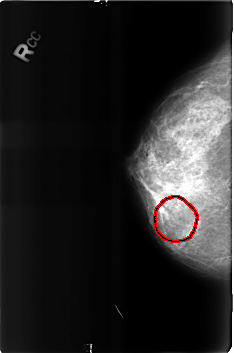

FILE: B_3160_1.RIGHT_CC.OVERLAY

TOTAL_ABNORMALITIES 1

ABNORMALITY 1

LESION_TYPE MASS SHAPE ROUND MARGINS N/A

ASSESSMENT 2

SUBTLETY 3

PATHOLOGY BENIGN

TOTAL_OUTLINES 1

BOUNDARY